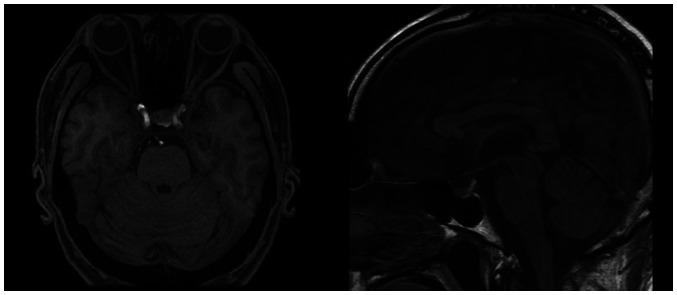

Immune checkpoint inhibitor (ICI) therapies have broadened the armamentarium for metastatic renal cell carcinoma (mRCC). As the ICI therapy spreads in the clinical settings, immune-related adverse events are more of a concern for clinicians. The present study reports three cases of mRCC treated with pembrolizumab plus axitinib and diagnosed hypopituitarism based on clinical symptoms and hormonal profile. Acute methylprednisolone infusion therapy was necessary in one case because of severe adrenal hypofunction; however, the clinical symptoms of the other two cases were controlled with oral corticosteroid therapy. To the best of our knowledge, there is no report of pembrolizumab plus axitinib related hypopituitarism in the treatment of mRCC. The present cases suggests that hypopituitarism after pembrolizumab plus axitinib treatment for mRCC can be handled with steroid therapy even after the development of hypopituitarism.

免疫检查点抑制剂(ICI)疗法拓宽了转移性肾细胞癌(mRCC)的治疗手段。随着ICI疗法在临床环境中的推广,免疫相关不良事件更受临床医生关注。本研究报告了3例接受派姆单抗加阿昔替尼治疗的mRCC病例,这些病例根据临床症状和激素水平诊断为垂体功能减退。其中1例因严重肾上腺功能减退需要急性甲泼尼龙输注治疗;然而,其他2例的临床症状通过口服糖皮质激素治疗得到控制。据我们所知,尚无关于派姆单抗加阿昔替尼治疗mRCC相关垂体功能减退的报道。本病例表明,mRCC患者接受派姆单抗加阿昔替尼治疗后发生垂体功能减退,即使在垂体功能减退发生后,也可用类固醇疗法处理。